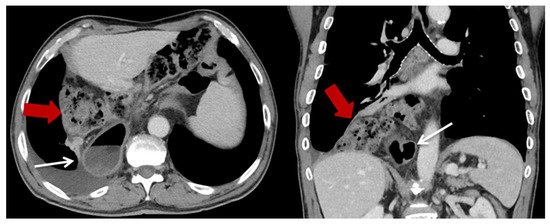

| Characteristics | HH (n = 23) (%) |

| Content of HH, n (%) | |

| Colon | 23 (100) |

| Additionally small bowel | 3 (13) |

| Position of the HH n (%) | |

| Left thoracic side | 18 (78.3) |

| Right thoracic side | 1 (4.4) |

| Both sides | 1 (4.4) |

| Lower mediastinum | 3 (13) |

| Symptoms n (%) | |

| None | 13 (56.5) |

| Abdominal pain and discomfort | 10 (43.5) |

| Ileus/incarceration | 4 (17.4) |